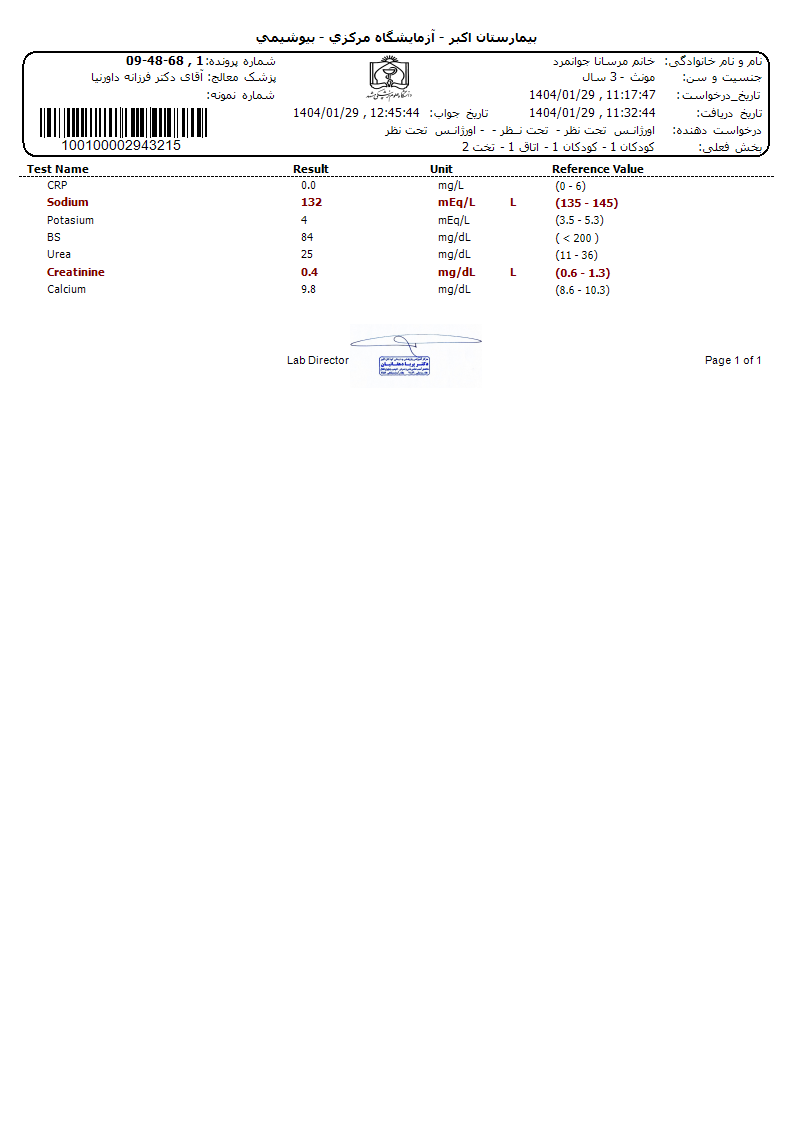

Other: